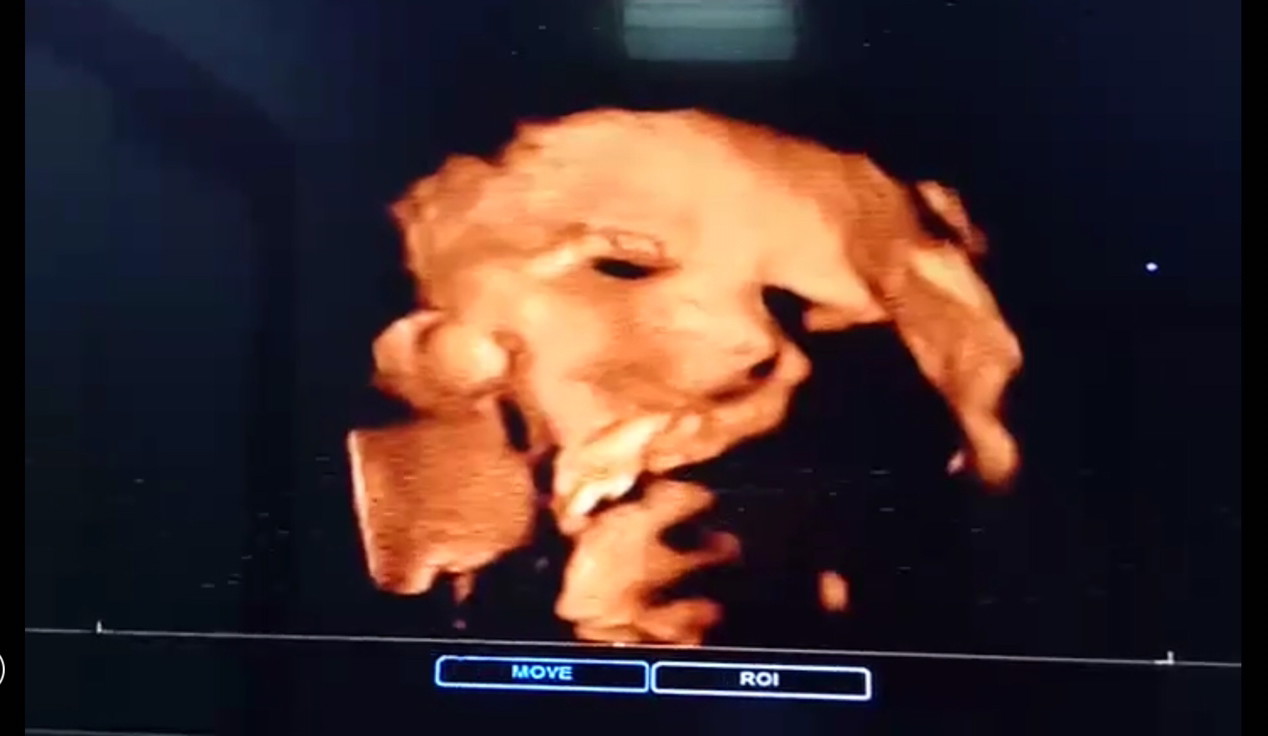

น้องมีตังค์คับ ตอนนี้ 34 w4 D แล้วคับ ตอนแม่ซาวดูผม ตอนนั้นผม 28 w คับ